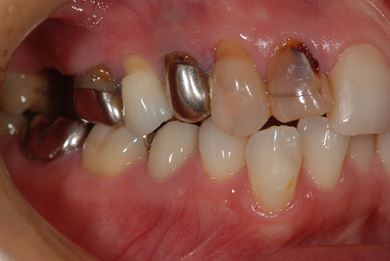

| 性別/年齢 | 女性 / 34歳 | ||||||||||||||||||||||||||||||||

| 主訴 | 現在痛みはなく、前歯の汚れを治したい。奥歯はブリッジを考えている。審美を考えているが、今治療をしたいというよりは、セラミックなど詳しいことがわからないので、計画や説明を伺いたい。 | ||||||||||||||||||||||||||||||||

| 治療方針 | 上前歯部分、セラミック治療にて審美的回復を行う。 | ||||||||||||||||||||||||||||||||

| 治療内容 | オールセラミッククラウン3本(オールセラミック用土台3本)、メタルボンドセラミッククラウン1本 | ||||||||||||||||||||||||||||||||

| 総治療費 | 562,800円 | ||||||||||||||||||||||||||||||||

| 治療期間 | 8ヶ月 |